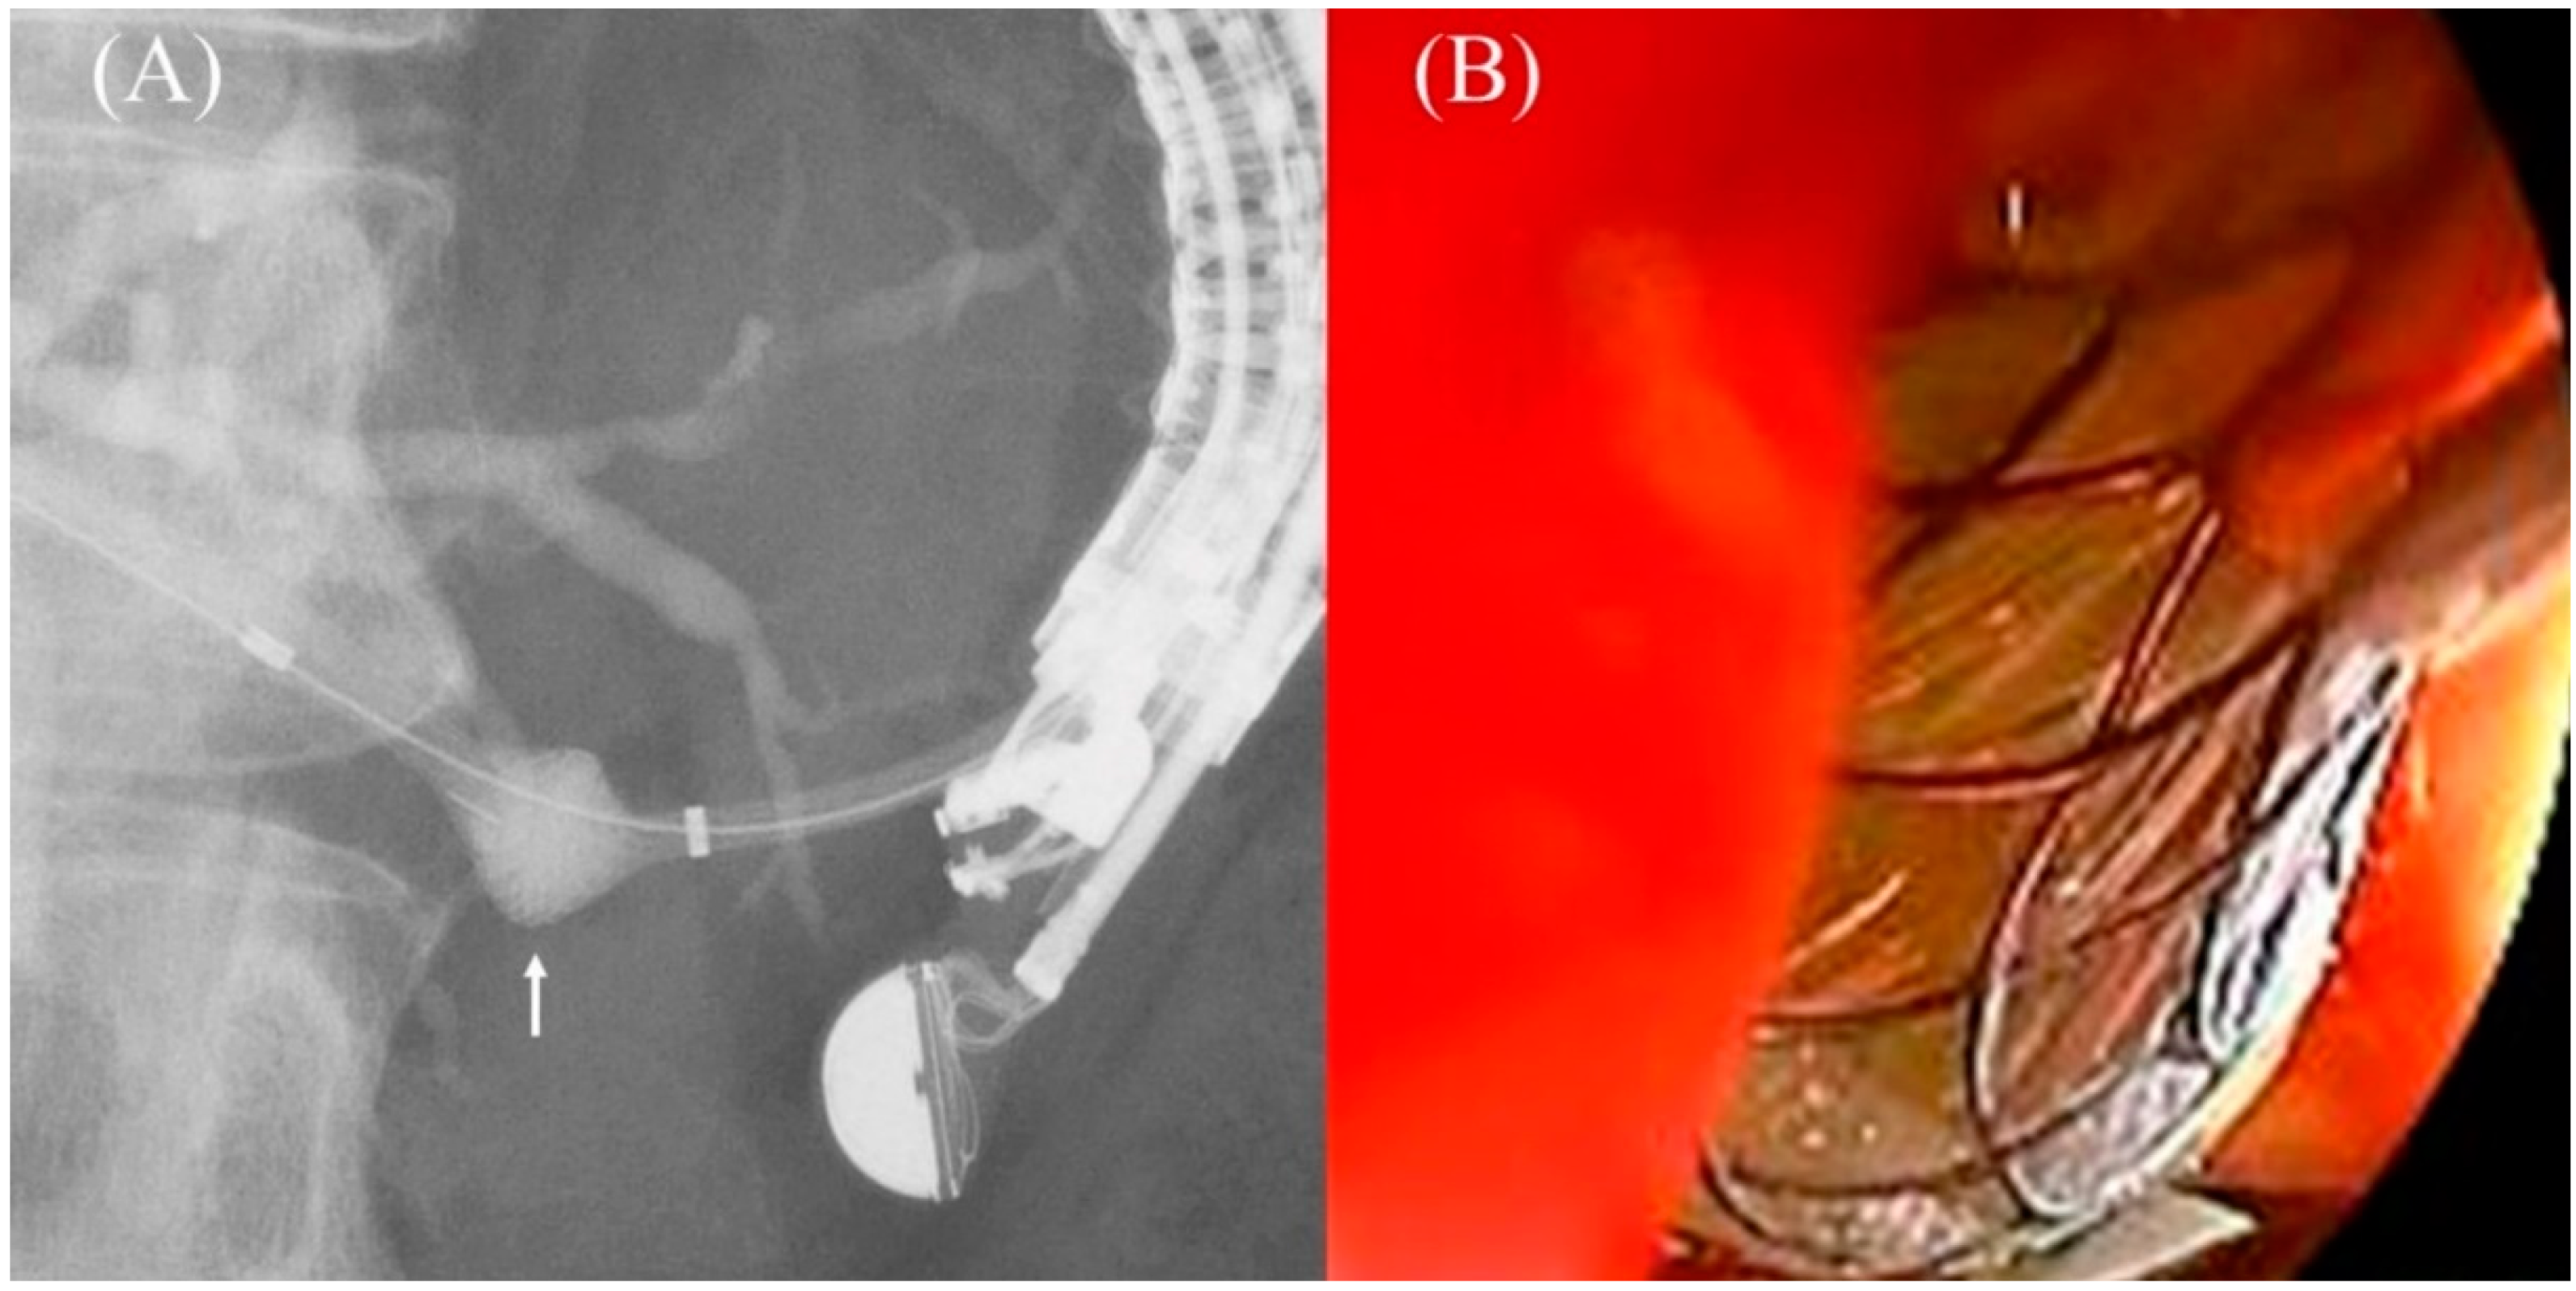

5.6. Stent Deployment